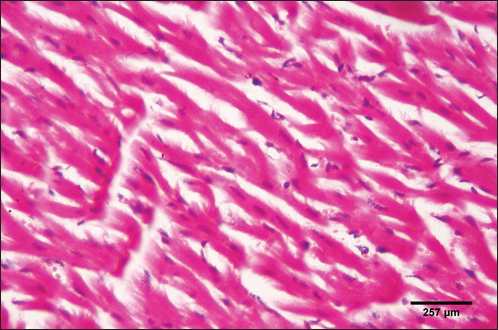

The histological structure of the cardiac myocytes was normal, with central oval nuclei and acidophilic sarcoplasm. In the intercellular gaps, a few tiny blood capillaries could be seen (Figs. 5 and 6). A cross-section of a proglottid of T. saginata revealing thick outer tegument, degenerating myocardiocytes surrounding it, and altered histological architecture was visible in the cardiac muscle tissue of infected calves. Mononuclear infiltration, cardiac oedema, and hemorrhage were all signs of a mild inflammatory reaction (Figs. 7 and 8).

Fig. 5. Photomicrograph of the ventricle of control cattle demonstration of a regular arrangement of cardiac muscle fibers, acidophilic sarcoplasm and central oval vesicular nuclei of the cardiac myocytes (H&E, low power).

Fig. 6. Photomicrograph of the ventricle of control cattle demonstration of normal cardiac myocytes with acidophilic sarcoplasm and central oval vesicular nuclei and normal histological appearance (H&E, high power).

Due to the early inflammatory response in cardiac muscle and the increased visibility of macroscopic lesions, the cardiac was validated as the ideal location for the diagnosis of cysticercosis (Scandrett et al., 2009). Heart inflammation brought on by the emergence of a pseudoepithelial boundary and a granulation tissue zone was the heart's reaction to the presence of C. bovis. Later, when the Cysticercus began to experience necrotic alterations, a new type of inflammatory response began to emerge (Sterba et al., 1979; Kumar et al., 2013). In the current investigation, routine H&E staining and histological analysis of the control group's heart muscles revealed a regular arrangement of cardiac muscle fibers with what appeared to be normal striations and branching. The histological results revealed significant alterations in the tissues of infected livestock. These findings are consistent with those of (Atteya et al., 2015), who demonstrated that microscopic lesions in the heart included cellular infiltration of lymphocytes, eosinophils, plasma cells and macrophages, necrosis of the tissue, proliferation of fibroblasts and development of granulation tissue along with the disintegration of cysts. Hashemnia et al. (2016) examined the ovine cysticercosis pathological lesions in sheep that had been killed. Severe degenerative and necrotic changes in the muscle fibers and also the sections of cysticerci in the affected organs were surrounded by a zone of degenerative, necrotic changes and polymorphonuclear leucocytes, lymphocytes, and fibroblasts were the predominant histopathological abnormalities. Abdel Aziz et al. (2022) showed that, severe fibrosis among cardiac muscles, fibrous tissue infiltrated with mononuclear inflammatory cells, and necrosis and atrophy in cardiac myocytes.